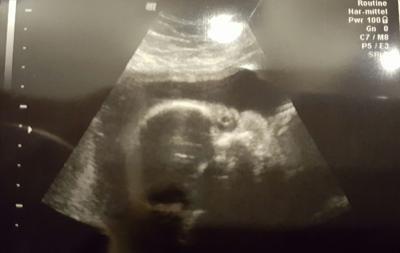

Es ist alles gut. Sie wiegt in etwa 920g. Sie liegt noch quer im bauch aber der arzt sagte sie hat noch genug platz zum drehen. Jetzt muss ich in 3 wochen hin da wird zuckertest gemacht ,mein erstes ctg und us. Der zuckertest geht zum glück auch nachmittags.

Bild zu War beim fa - Forum für Mai - Mamis